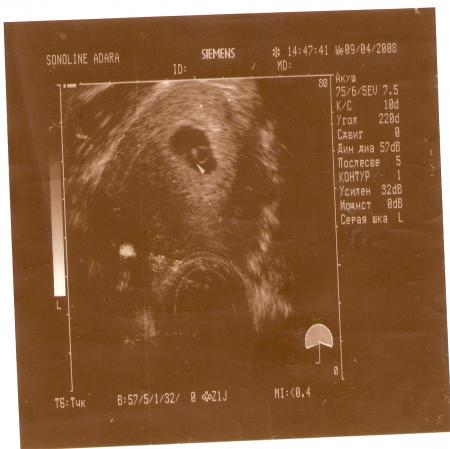

Первое фото малыша. Срок 4-5 недель

Там куда показывает стрелочка и находиться мой малыш.

Мне делали вагинальным датчиком, поэтому хорошо видно. А так...рано в принципе УЗИ делать. Я просто вытерпеть не смогла.:)))